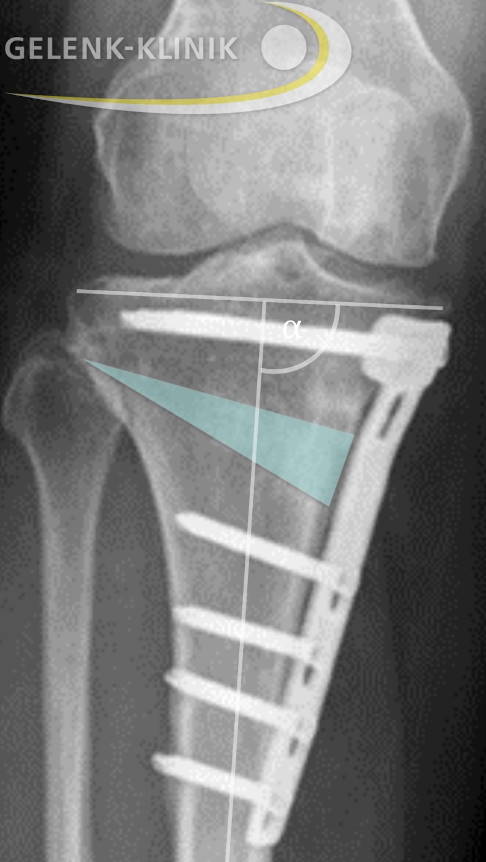

Bei der O-Bein-Stellung wird das Schienbein (Tibia) über einen Schnitt auf der Innenseite des kniegelenknahen Unterschenkels fast komplett durchtrennt. Nachfolgend klappt der Orthopäde das Schienbein schonend keilformig auf, bis die gewünschte Position erreicht ist. Eine spezielle winkelstabile Platte aus Titan und Schrauben sichert und fixiert diesen Schnitt im Knochen. Den Eingriff bezeichnet man als öffnende Umstellungsosteotomie oder Open-Wedge-Technik.

Etwa 4 Wochen nach der Umstellungsosteotomie erfolgt eine Röntgenkontrolle. Danach kann der Patient stückweise zur Vollbelastung des operierten Beins übergehen. Spätestens nach 6 Wochen sollte die Vollbelastung erreicht sein. Dann ist auch das Training an Geräten zum Muskelaufbau gut möglich. 12 bis 18 Monate nach der Umstellungsosteotomie entfernt der Orthopäde die eingesetzten Platten und Schrauben.